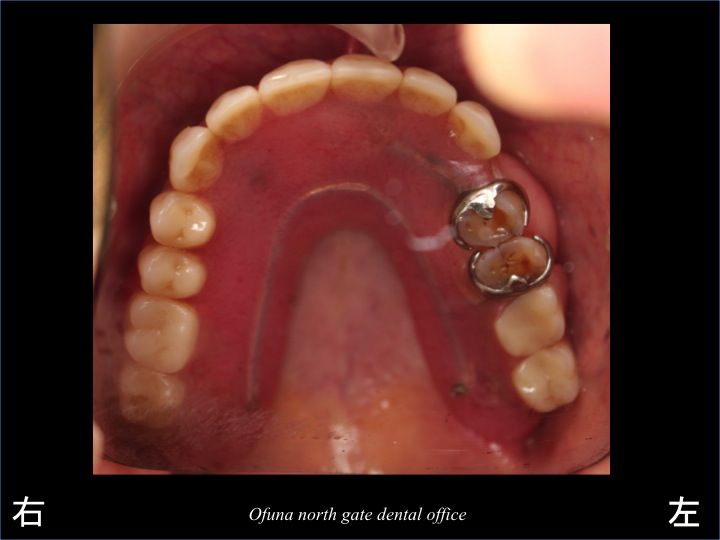

今回の治療前のレントゲンが以下になります。

上顎の左側に2歯分歯が残っています。

この残っている歯に義歯の金具を付けて使用しています。